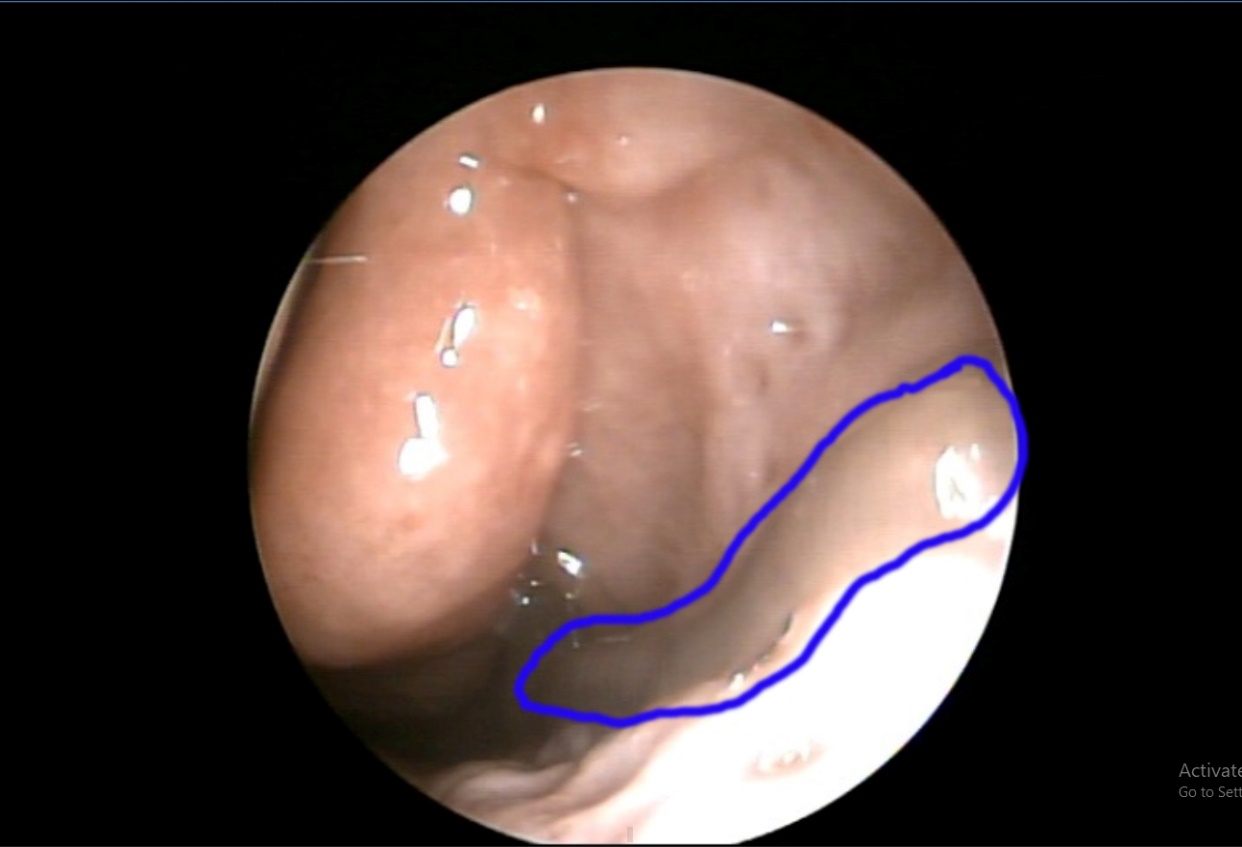

Hình ảnh nội soi con tặc trông hốc mũi bệnh nhân

Vừa qua, TTYT huyện Chiêm Hoá đã thực hiện ca nội soi và gắp thành công hai con vắt sống trong mũi một bệnh nhân. Bệnh nhân nữ, 63 tuổi, sinh sống tại xã Yên Lập đến khám với tình trạng thường xuyên ngạt mũi, chảy máu cam từ hai mũi, số lượng ít và tự cầm máu. Qua thăm khám và nội soi, phát hiện trong hốc mũi phải và hốc mũi trái bệnh nhân có hai con tặc còn sống. Các bác sĩ đã lấy con tặc ra khỏi mũi bệnh nhân, chiều dài khoảng 4 cm.